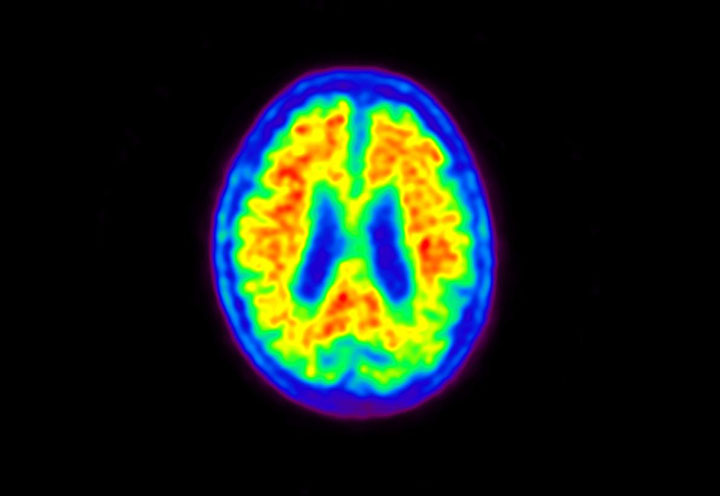

Head / Case5 : Amyloid

Courtesy : Kindai University Hospital

- Imaging protocol

- Injected dose: 4.27 MBq/kg, 18F-Flutemetamol

- Uptake time: 99 minutes

- Scan time: 20 minutes